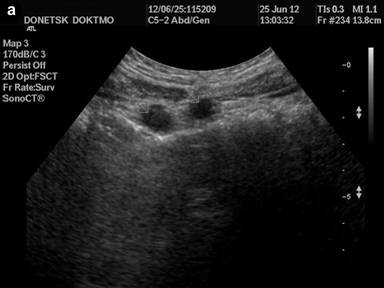

Ultrasound diagnostics (Figure 2а, b): no free fluid in the abdominal cavity and pleural sinuses. Liver: total size (left and right lobe) - not increased, smooth circuit, capsule is not thickened, no signs of hepatoomentopexy, total echogenicity - normal, no focal changes. Portal vein - 0.9 cm in diameter, blood velocity 24.0-30.0 cm/s, hepatopetal undulating blood flow. Hepatic artery: blood velocity - to 80.0 cm/s, low-resistant type of blood flow. Induration of the round ligament of the liver with the presence of effect of distal attenuation from it, without signs of recanalization. Gall bladder - common anatomical location, form, circuit, volume; wall - not thickened. Choledochus - 0.3 cm in diameter. No concrements. Pancreas - no liquid collectors in the projection of omental bursa, total volume is not increased, smooth circuit, echogenicity is slightly increased, in the projection of the cervix - body not dilated Wirsung’s duct is visualized (0.2 cm in diameter). Spleen - rejected. Closer to the anterior abdominal wall, near the border of the parietal peritoneum - 3 solid rounded formations, transversely located in the epigastrium, at the distance of up to 2.0 cm apart from each other, hypoechoic, with a smooth circuit, homogeneous structure, upon energy mapping at the "noise" border - with single loci of blood flow, moderately movable during instrumental palpation, movable upon respiratory excursion. Kidneys, adrenal glands - without visible pathological changes.

Figure 2 а, b. Ultrasound diagnostics of the organs of abdominal cavity. Closer to the anterior abdominal wall, near the border of the parietal peritoneum - 3 solid rounded hypoechoic formations, transversely located in the epigastrium, with smooth circuits, homogeneous structure. |